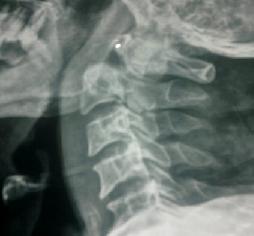

Odantoid Fracture

Facet Dislocation

Tubercular Spondilytis

Cervical Vertebral Fracture

Vertebral Injury

Cervical Cord Compression